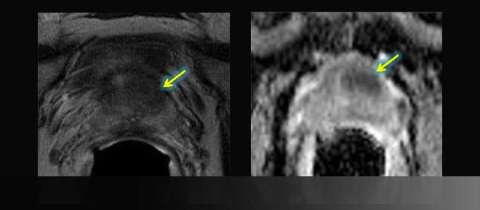

LEFT: Axial T2-weighted image: asymmetric anterior low signal

RIGHT: Apparent diffusion coefficient (ADC) map: focal restricted diffusion